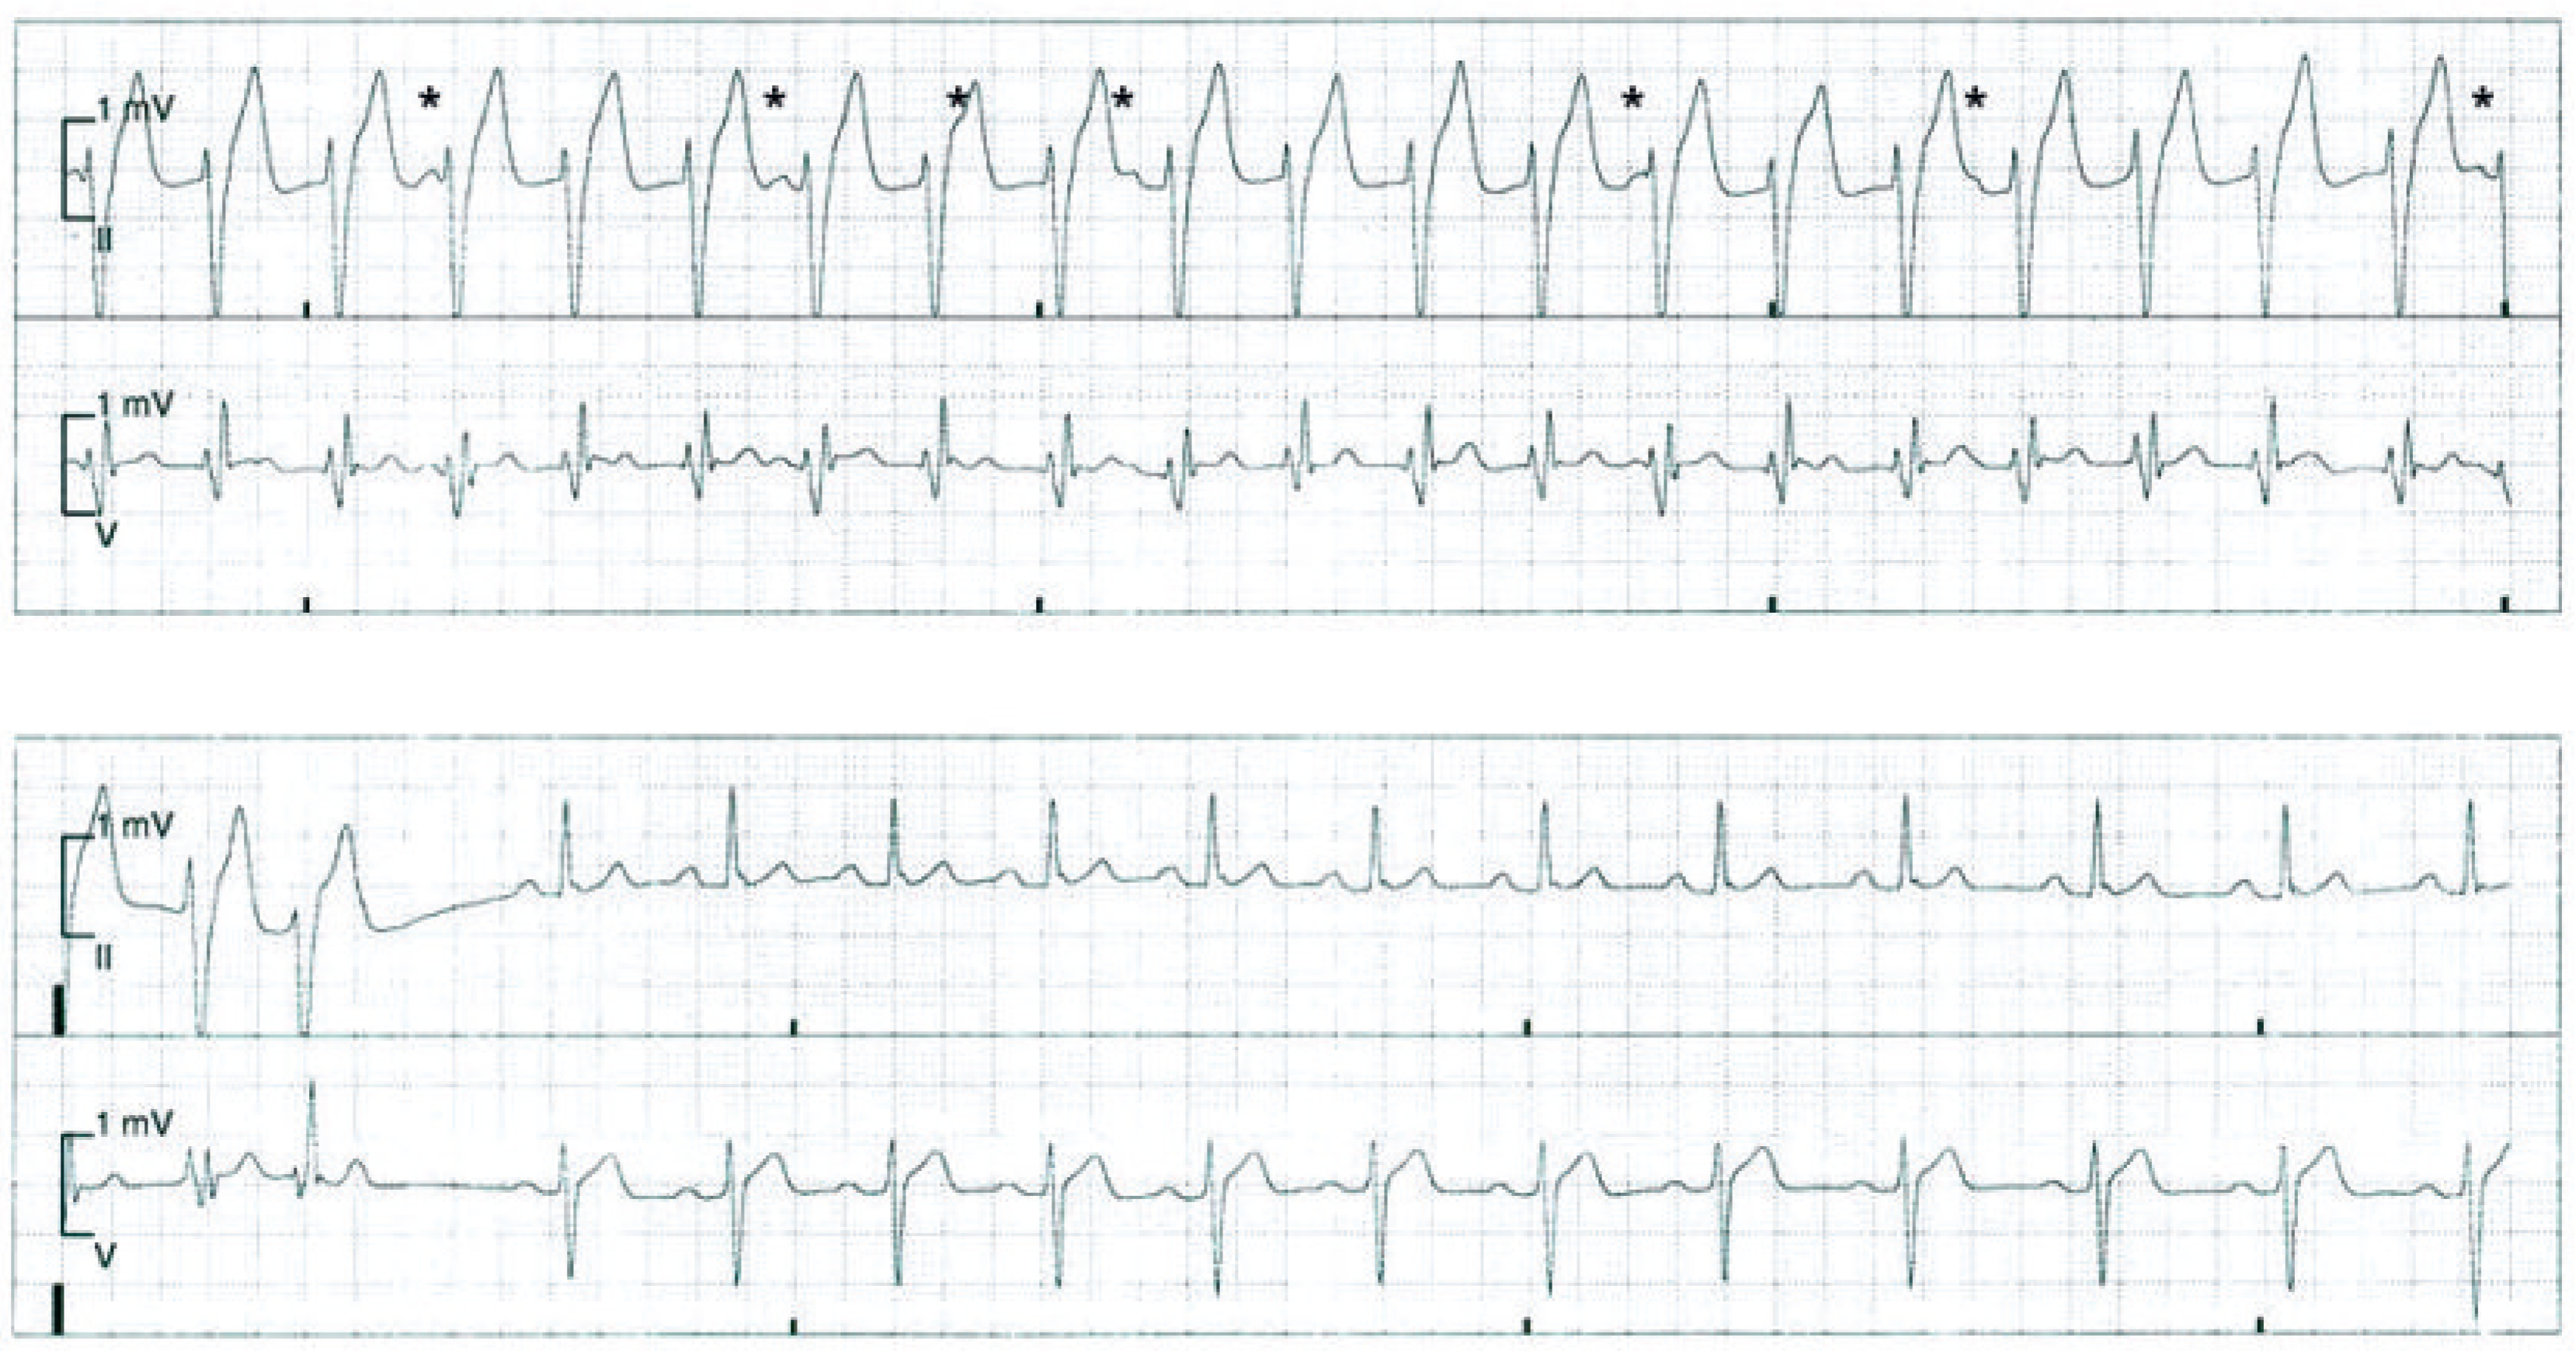

Nach einem erfolglosen Valsalva-Manöver sowie einer Carotis-Sinus-Massage wurde fraktioniert 10 mg Metoprolol intravenös verabreicht. Dadurch konnte jedoch keine Senkung der Frequenz erreicht werden, sodass der Patient zur weiteren medikamentösen Therapie der Tachykardie auf die Überwachungsstation verlegt wurde, wo unter Monitor-Kontrolle ein intravenöser Bolus von 12 mg Adenosin appliziert wurde. Auch darunter kam es zu keiner Terminierung der Tachykardie. Erst nach der Gabe von 5 mg Verapamil intravenös konnte die Tachykardie schliesslich terminiert werden (Abb. 2). Während der anschliessenden Überwachung war der Patient allezeit hämodynamisch stabil und im EKG zeigte sich ein normokarder Sinusrhythmus.

Die rechtsschenkelblockartige Morphologie mit einer leicht verlängerten QRS-Dauer von 130 ms sowie der überdrehte Linkslagetyp deuten darauf hin, dass es sich in diesem Fall um eine idiopathische ventrikuläre Tachykardie aus dem linken posterioren Faszikel handelt, welche üblicherweise auf Verapamil anspricht. Der Arrhythmie liegt ein Reentry-Mechanismus im linken posterioren Faszikel zugrunde [1]. Aufgrund des Ursprungsorts in den Purkinje-Zellen des Faszikels ist die QRS-Verbreiterung nur wenig ausgeprägt (120 ms bis 160 ms). Selten entspringt die Tachykardie aus dem anterioren Faszikel des linken Schenkels und dann findet sich eine überdrehte Rechtsachse des QRS-Vektors. Das fehlende Ansprechen auf Adenosin ist als schwacher Hinweis und nicht als diagnostischer Test zu werten, dass es sich um keine supraventrikuläre Tachykardie im klassischen Sinne handelt. Im Tachykardie-EKG findet sich eine atrio-ventrikuläre Dissoziation, was den ventrikulären Ursprung der Tachykardie bestätigt (Abb. 2).

Abbildung 2.

Terminierung der Tachykardie unter Verapamil. Während der Tachykardie kann eine atrio- ventrikuläre Dissoziation dokumentiert werden. Die dissoziierten P-Wellen sind mit einem «Sternchen» gekenn- zeichnet.